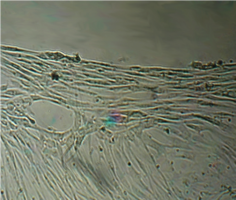

На всей остальной поверхности дна опытной чашки монослой был целостным и равномерным, фибробласты сохраняли обычную структуру, форму и размеры.

Вид монослоя и структура клеток не отличались от обычных в течение всех четырех суток наблюдения.

Количество поврежденных клеток было в пределах 2-5%.

Монослой оставался целостностным и равномерным на всей поверхности чашки Петри, клетки вблизи образца сохраняли характерное для культуры фибробластов взаимное расположение и направление роста (рис. 39).

Морфология их также соответствовала сроку роста: клетки веретеновидной формы с гомогенной цитоплазмой и центрально расположенным пузырьковидным ядром неплотно прилежали друг к другу и анастомозировали своими отростками.

В последующие сроки мы также не наблюдали каких-либо морфологических признаков воздействия имплантата на культуру фибробластов.

Клетки формировали равномерный монослой, плотность которого соответствовала сроку роста культуры после пассирования и не зависела от расстояния до образца (таб. 17).